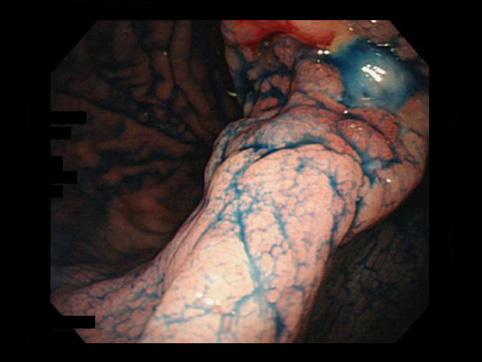

질환(병리주체)의 분류 악성 상피성종양/선암

부위(장기별) 위(부위)/위각

검사방법 내시경

종양의 육안분류 3형(궤양침윤형)/

종양의 최대경(밀리미터) 30~34

종양의 심달도 ss(a1)